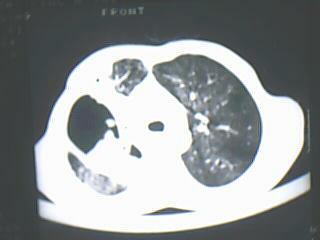

以下是引用随光逐影在2009-8-7 15:40:00的发言:[br]考虑右肺继发性肺结核并右肺上叶空洞形成,两肺支气管播散;不排除右肺上叶空洞内霉菌感染可能。

以下是引用jiangjing在2009-8-7 14:38:00的发言:[br]右上肺张力空洞,酐珞坏死灶,支气管扩张,多发播散灶,纵膈淋巴结显示,胸膜增厚---结核